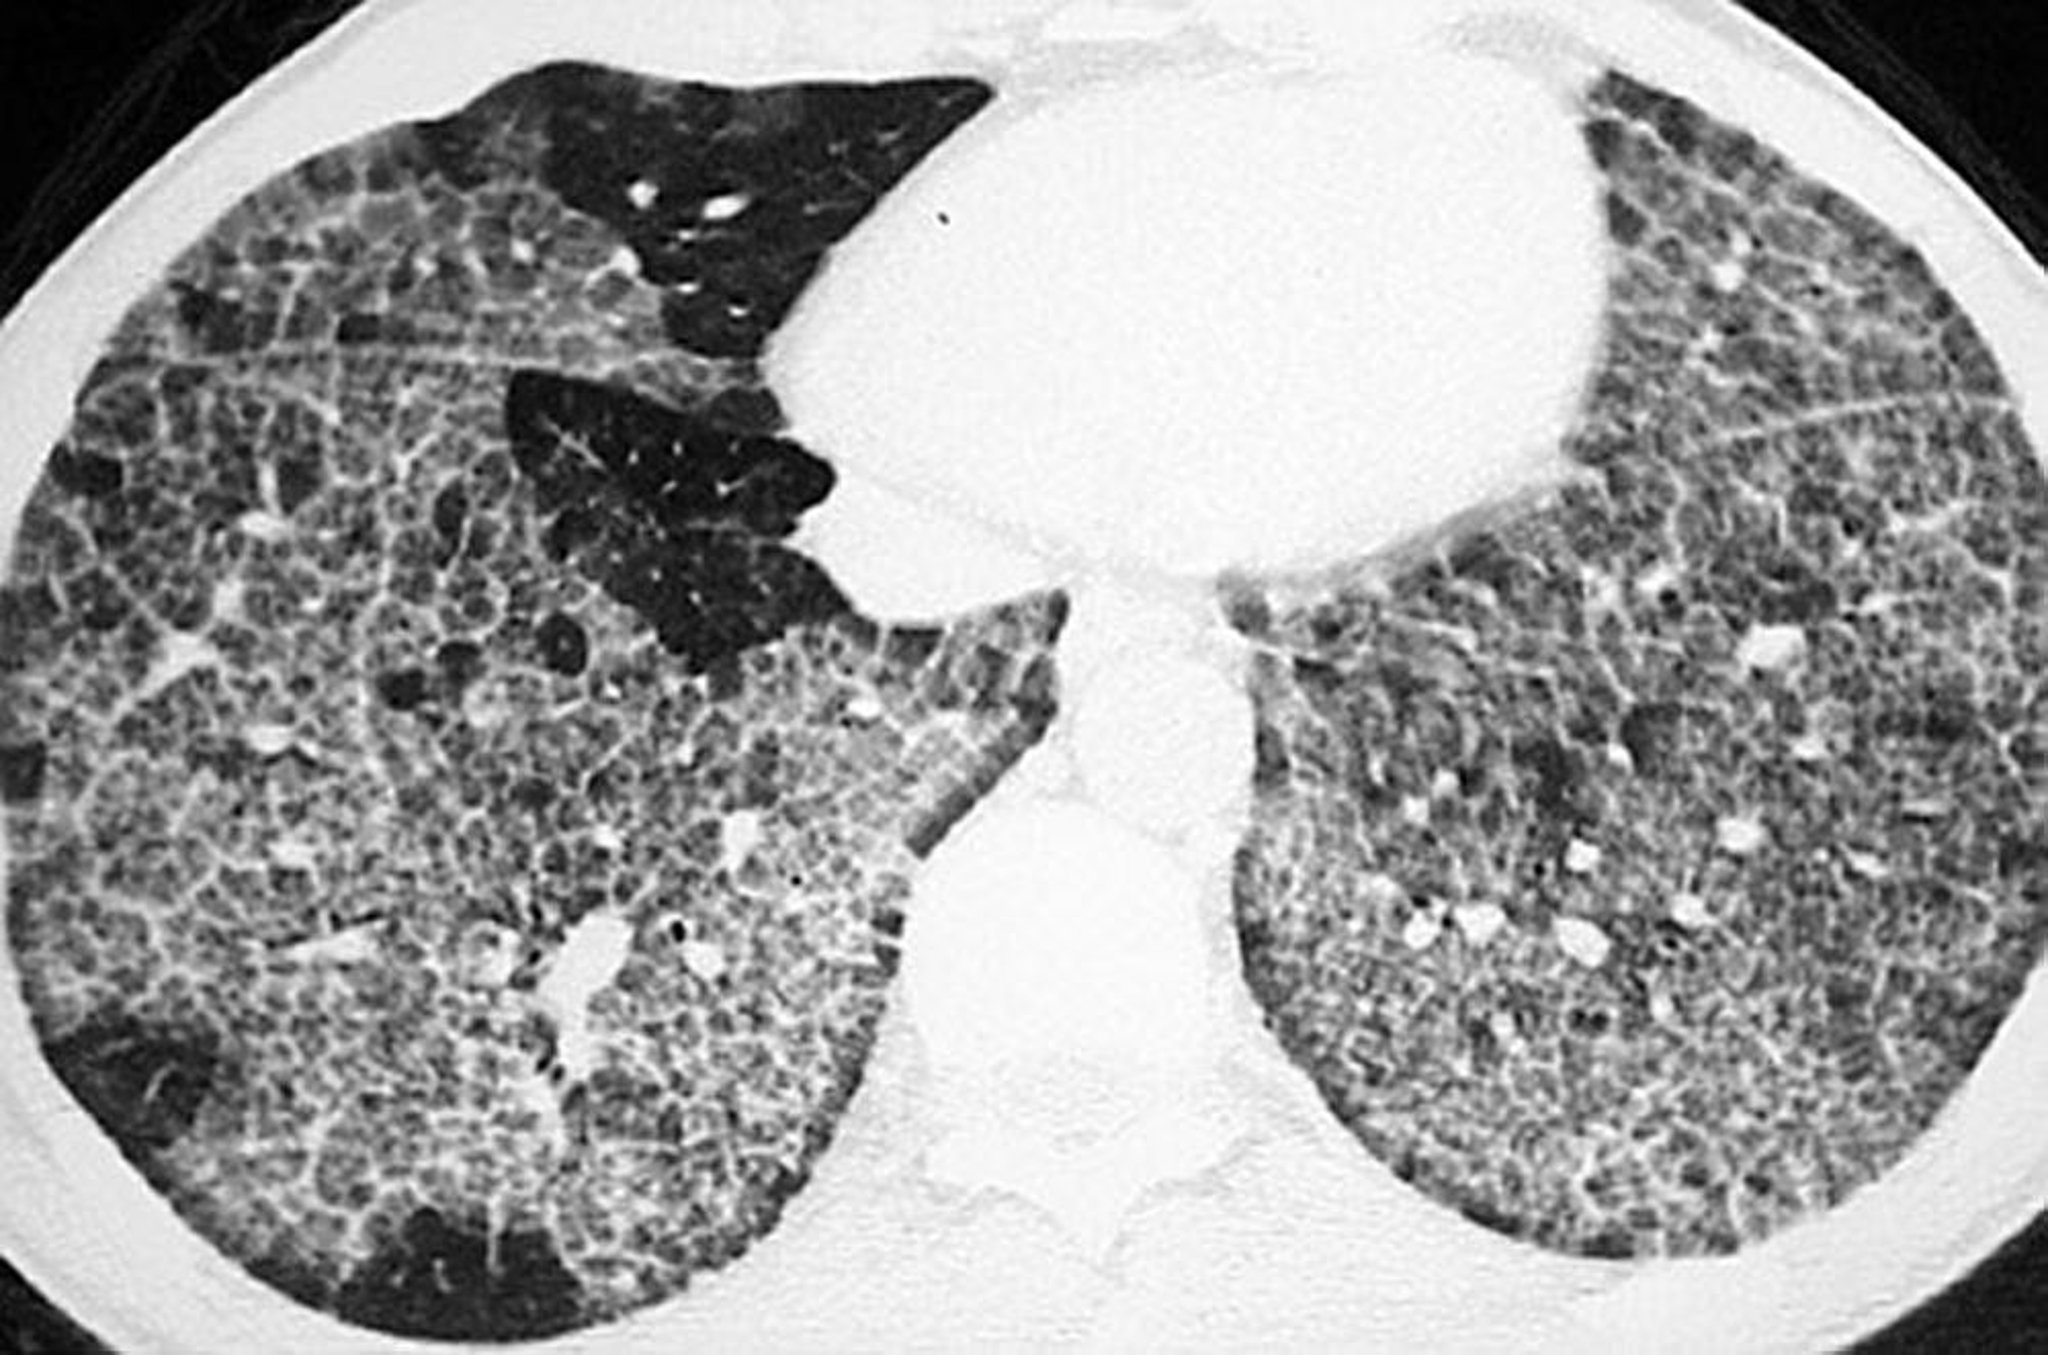

Proteinosis alveolar pulmonar (tomografía computarizada)

Tomografía computarizada de alta resolución que muestra opacificación en vidrio esmerilado y tabiques y estructuras intralobulillares engrosadas con forma poligonal ("en pavimento irregular").

Image courtesy of Talmadge E. King, MD.